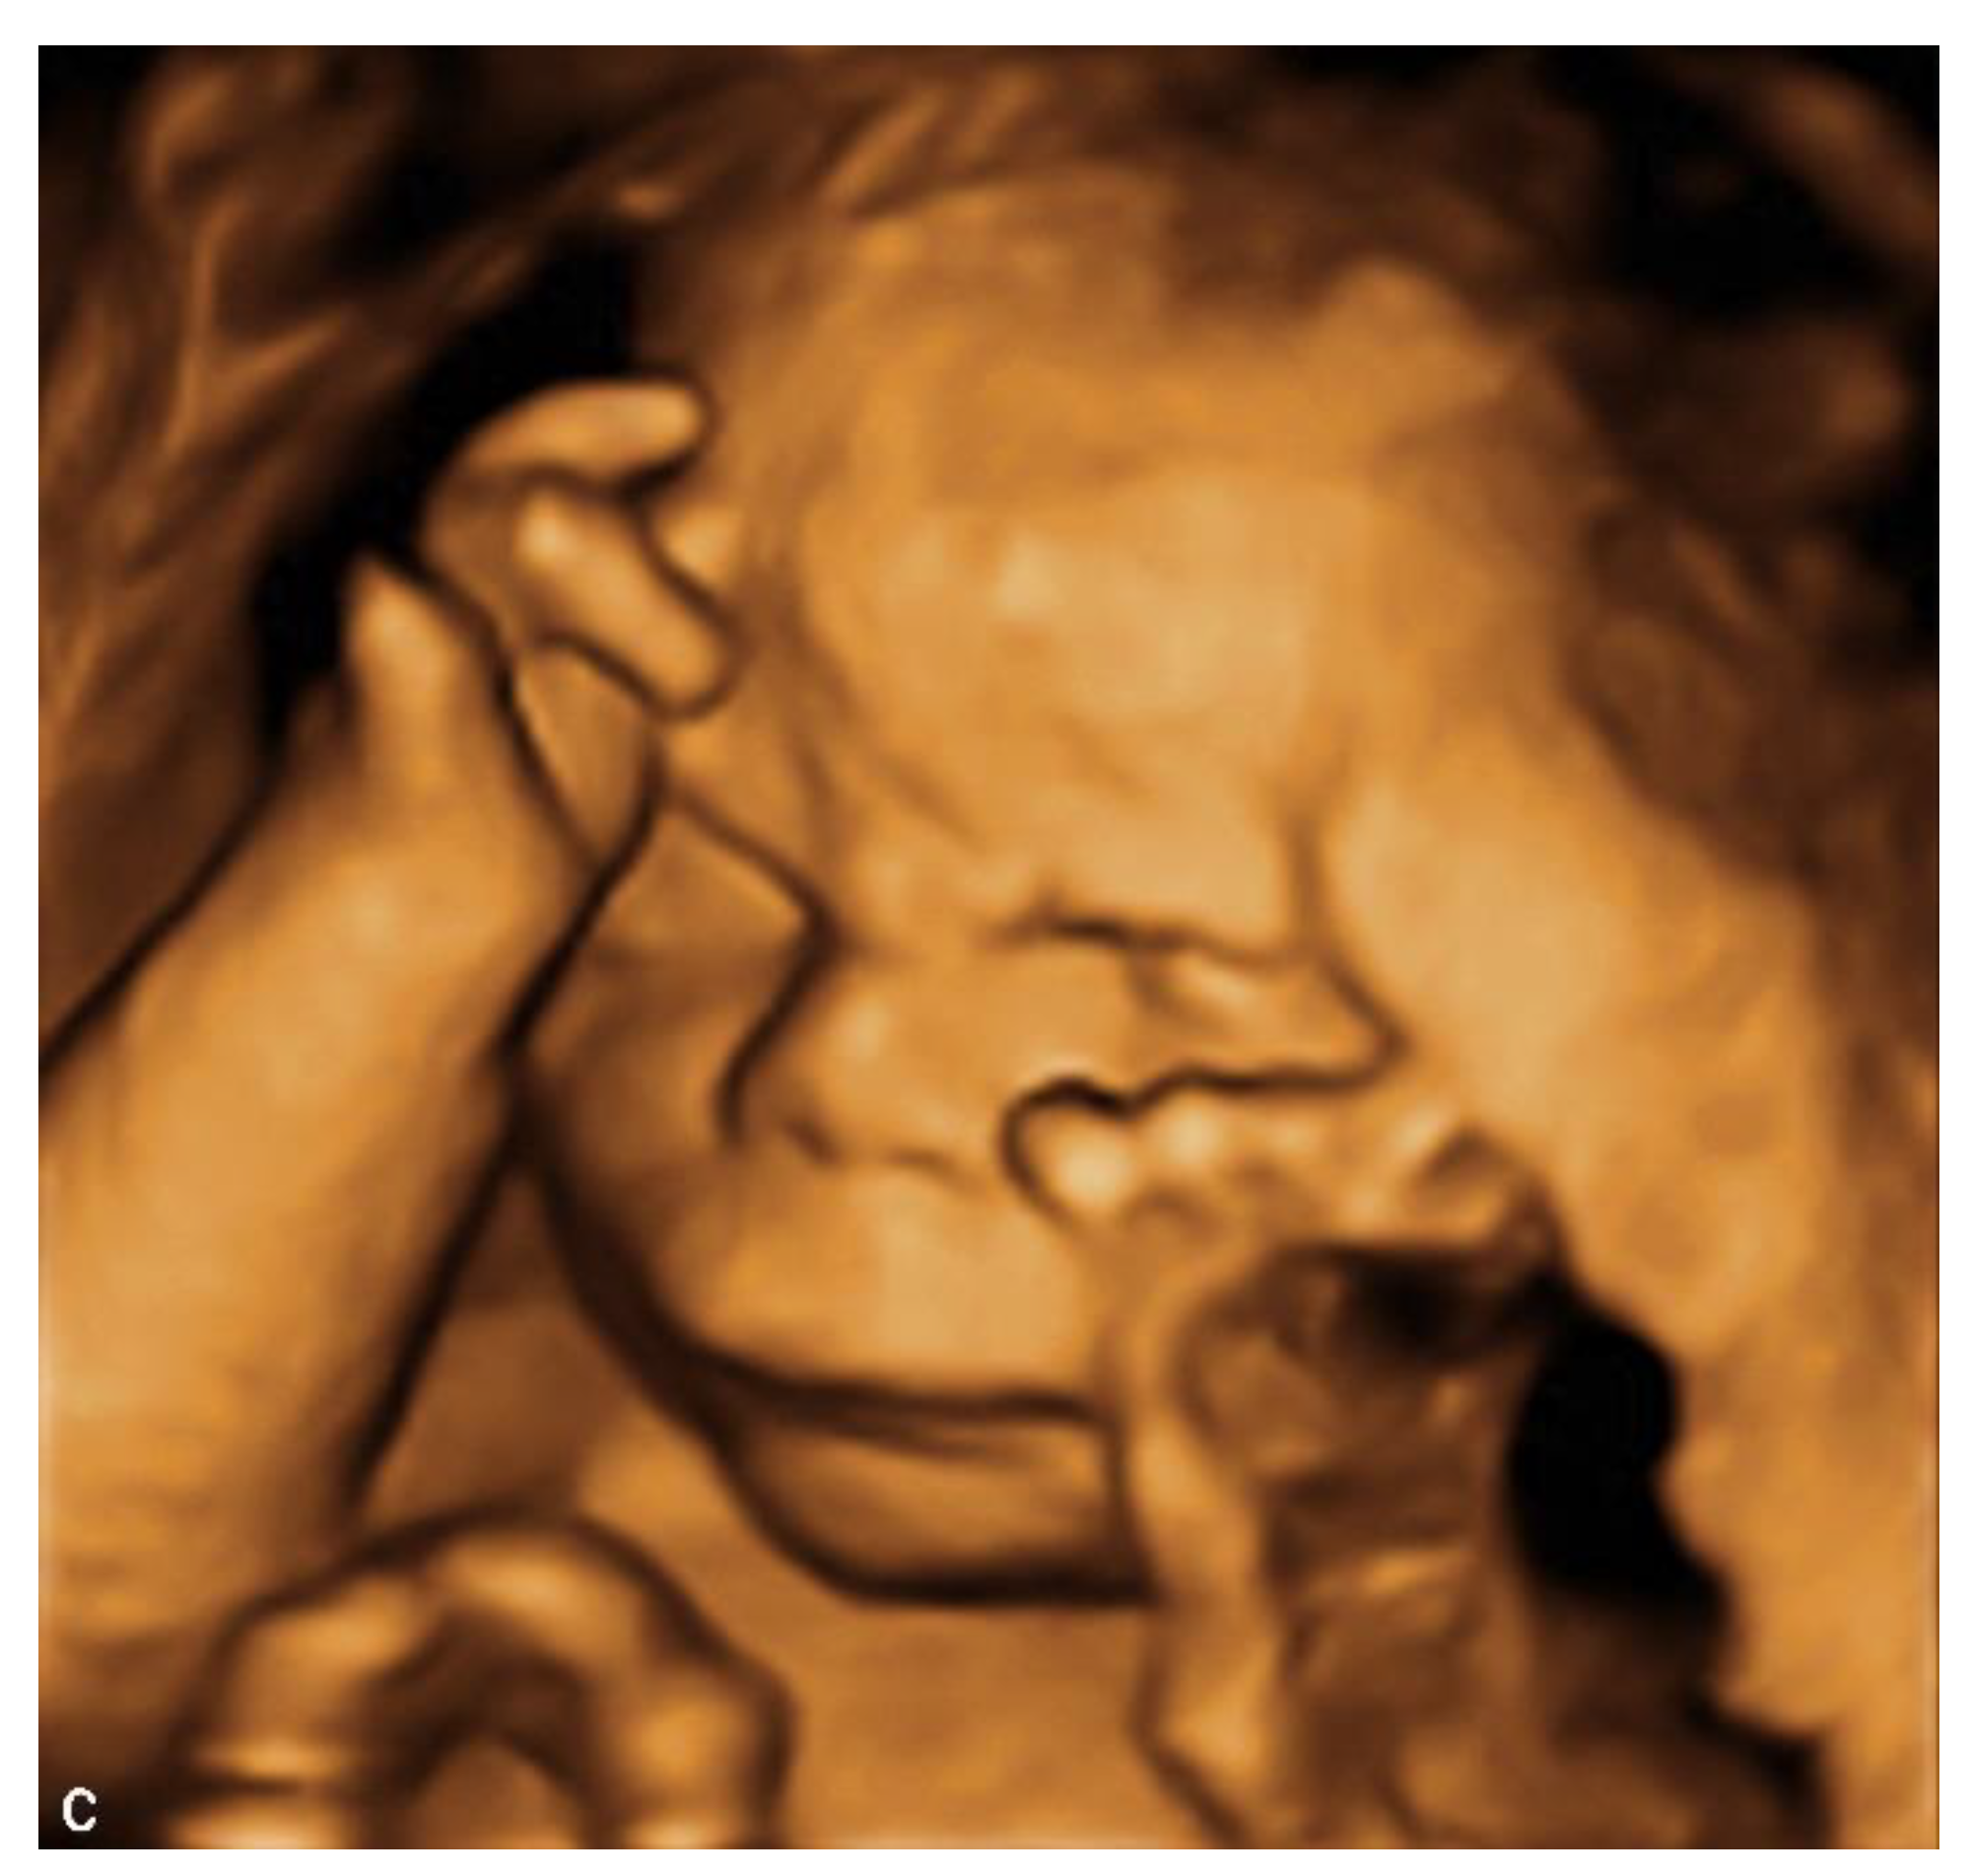

4. Prenatal Presentation of a Classical CDLS Case

We report a case of prenatal diagnosis of CDLS at 29 weeks’ gestation in a 30-year-old woman who had previously delivered a normal baby. The patient was referred to our fetal medicine unit because of fetal growth restriction, diagnosed at 24 weeks’ gestation. As no Doppler flow anomalies were detected, a genetic anomaly (lethal trisomy) rather than placental insufficiency was suspected by the referring doctors. Ultrasound examination in our unit demonstrated symmetrical fetal growth restriction with normal Doppler studies. The amniotic fluid was increased with a deepest vertical pool of 9.2 cm. Examination of the fetal face showed abnormal profile, synophrys, depressed nasal bridge, long downturned upper lip, and micrognathia (Figure 1A,B). Cardiac examination demonstrated abnormal flow through the atrio-ventricular, aortic, and pulmonary valves. The third finger of the right fetal hand was missing, and the fingers of the left hand were overlapping.

Figure 1.

Ultrasound examination of the fetal face in a CDLS case with classical phenotype: (A) 2D image of the fetal profile at 29 w of gestation, showing mild micrognathia/retrognathia; abnormal philtrum; depressed nasal bridge; (B) Volume reconstruction of the fetal face at 29 w of gestation; (C) Volume reconstruction of the fetal face at 34 w of gestation.

The initial ultrasound findings persisted in the third trimester (Figure 1C). As pregnancy progressed the polyhidramnios worsened but did not become tense and did not require amniodrainage. Fetal skin edema was seen in late pregnancy.